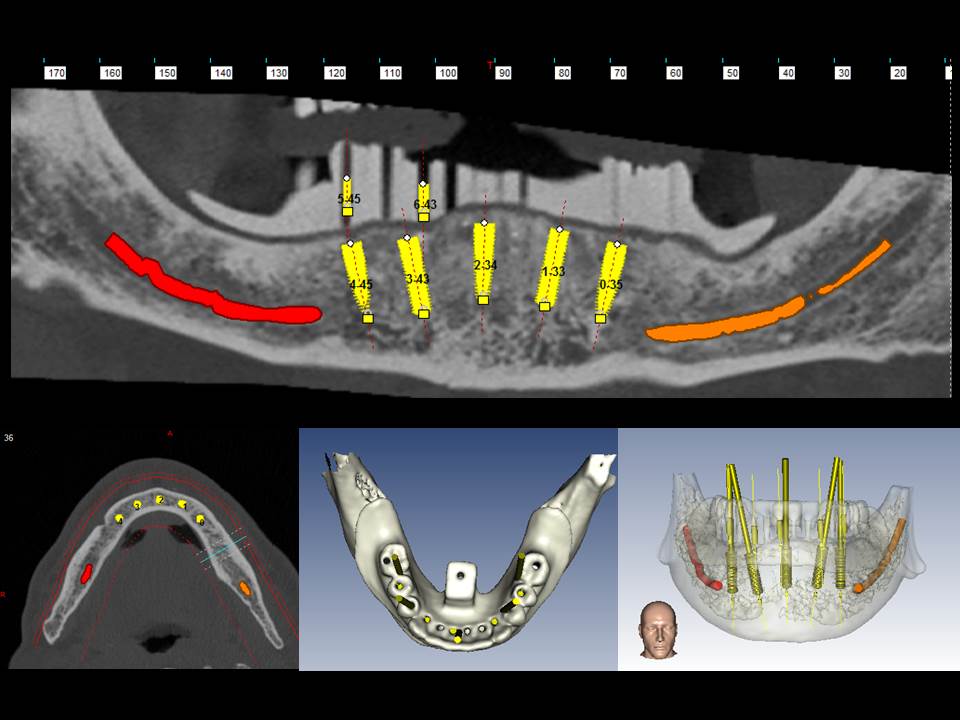

Prótesis fija OT BRIDGE

CASOS CLÍNICOS